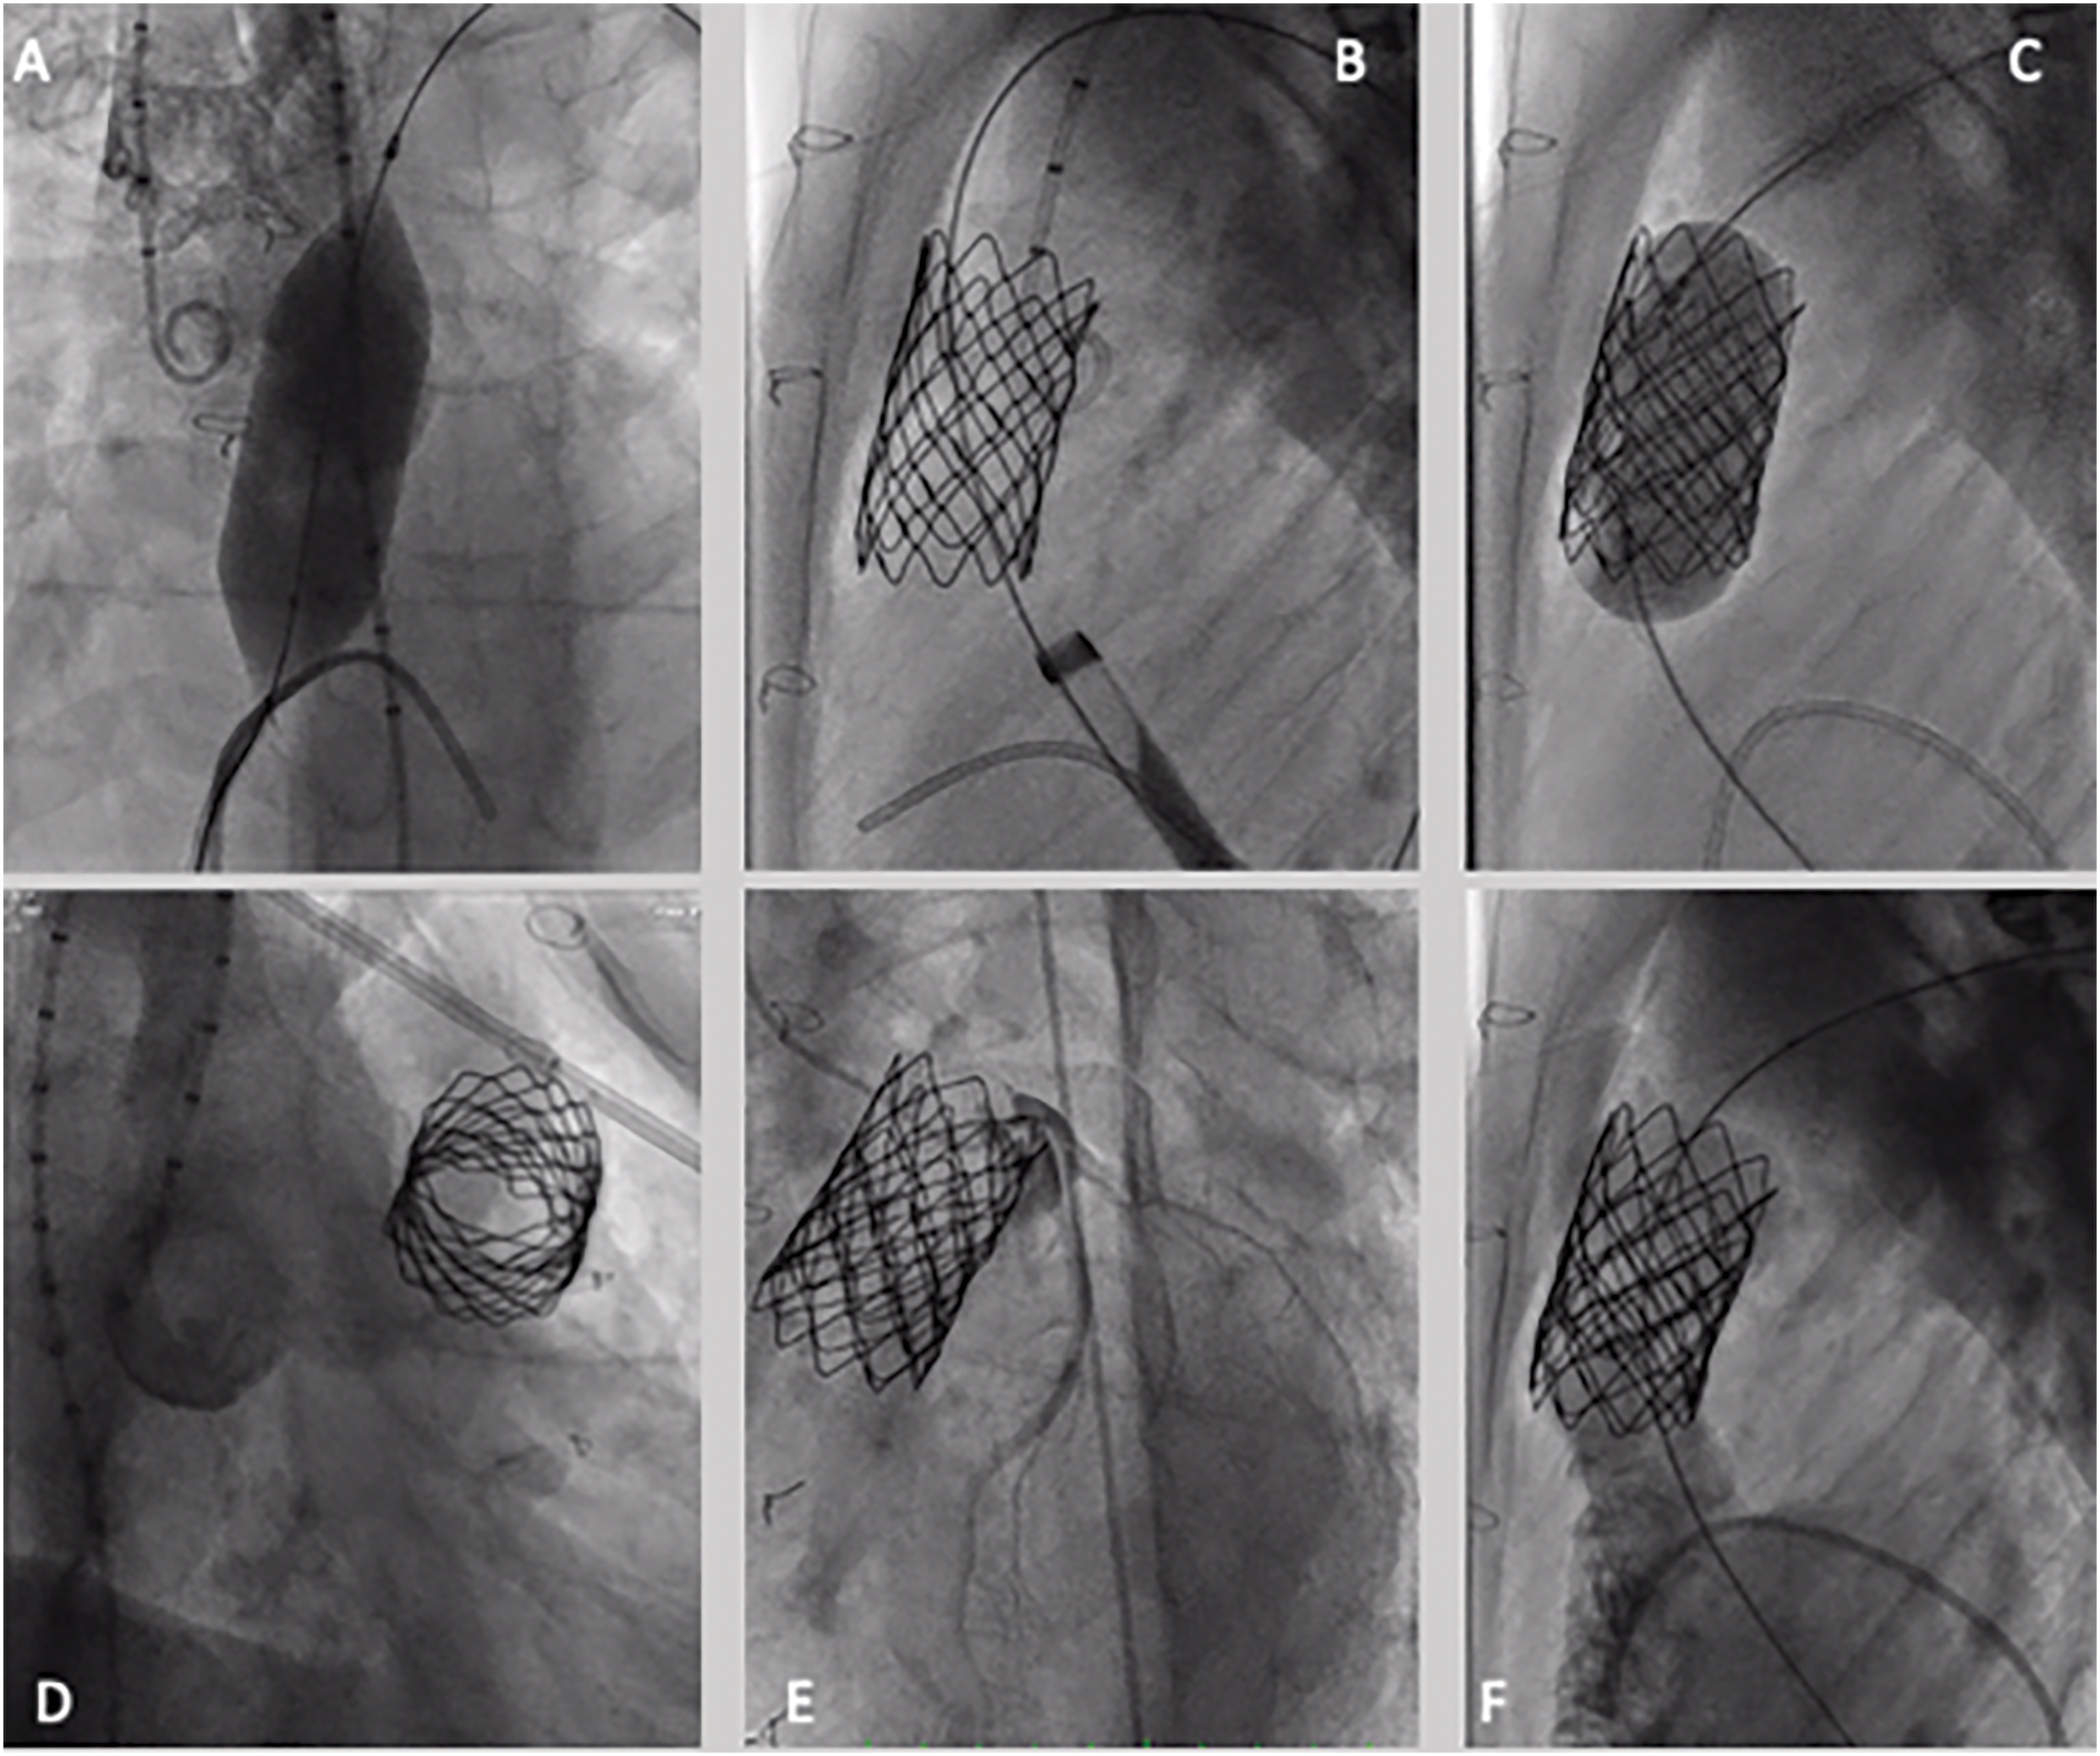

Once the valve is in position the sheath is retracted to uncover the valve. Deployment is completed by sequentially inflating the inner balloon first, followed by inflation of the outer balloon. The ensemble is 22 Fr large. It can be effectively used bare in the vein, over a stiff exchange guidewire (Fig. 1). Once the valve is delivered, an 18 Fr sheath can replace it without risk of local bleeding. Alternatively, it can be delivered through a 24 or 26 Fr Gore®® Dry Seal long-sheath.

Figure 1: Melody valve implantation—step-by-step procedure. (A) Conduit ballon interrogation, aortic root, and non-selective coronary interrogation by using a 22 mm × 40 mm atlas gold balloon; (B) presenting of RVOT with a CP stent mounted on a 22 mm × 40 mm atlas gold balloon; (C) 18–10 Melody valve deployment, mounted on a 22 mm ensemble; (D) aortic angiography after valve deployment, demonstrating no regurgitation; (E) selective coronary angiography after valve deployment, no coronary compression; (F) pulmonary angiography demonstrating no regurgitation or paravalvular leak